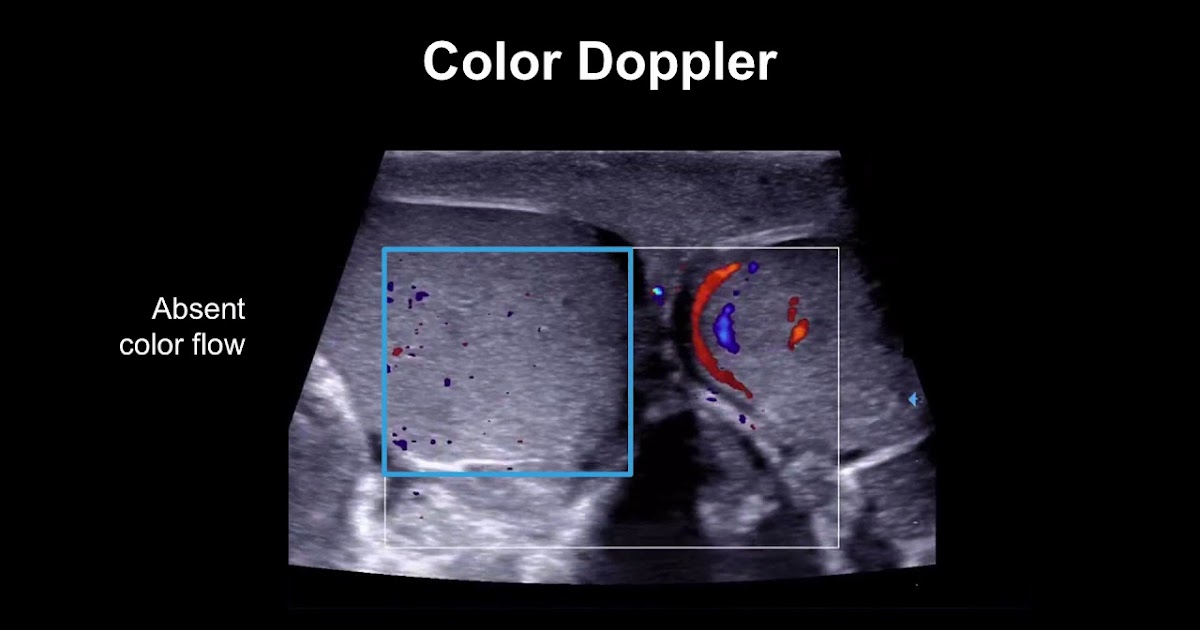

Testicular Torsion Ultrasound  Web  when there is a low suspicion of testicular torsion, color doppler and power doppler ultrasonography can be used to demonstrate arterial. This activity will review the most common causes of testicular. Web prompt doppler ultrasonography to aid in diagnosis is often key to managing testicular torsion, but there may be delays in. Web  when there is a low suspicion of testicular torsion, color doppler and power doppler ultrasonography can be used to demonstrate arterial. Web  ultrasound is the ideal imaging modality to evaluate the scrotal contents. Web  testicular torsion has been reported to have a bimodal distribution, an initial peak in the first year of age where. Web this study analyzes the sonographic characteristics of testicular torsion in 46 patients and categorizes them into six. Web learn about the clinical presentation, differential diagnosis, and imaging studies of testicular torsion, a surgical emergency affecting young males.

Testicular torsion color Doppler ultrasonography. An echopenic right Testicular Torsion Ultrasound  Web  ultrasound is the ideal imaging modality to evaluate the scrotal contents. Web  when there is a low suspicion of testicular torsion, color doppler and power doppler ultrasonography can be used to demonstrate arterial. Web this study analyzes the sonographic characteristics of testicular torsion in 46 patients and categorizes them into six. Web prompt doppler ultrasonography to aid in diagnosis. Testicular Torsion Ultrasound.